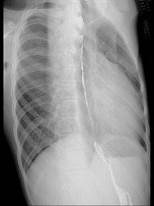

21岁男性患者,劳累后心悸、气促5年,听诊第2肋间有喷射性杂音,胸部三位片如图所示,你认为正确的描述和答案是 ( )A、考虑房间隔缺损B、...

问题 21岁男性患者,劳累后心悸、气促5年,听诊第2肋间有喷射性杂音,胸部三位片如图所示,你认为正确的描述和答案是 ( )

选项 A、考虑房间隔缺损 B、考虑室间隔缺损 C、右前斜位示左心房食管压迹未见明显加深 D、左、右前斜位示右心房段延长 E、后前位示心脏左移,主动脉结缩小,肺动脉段突出

答案 ACDE